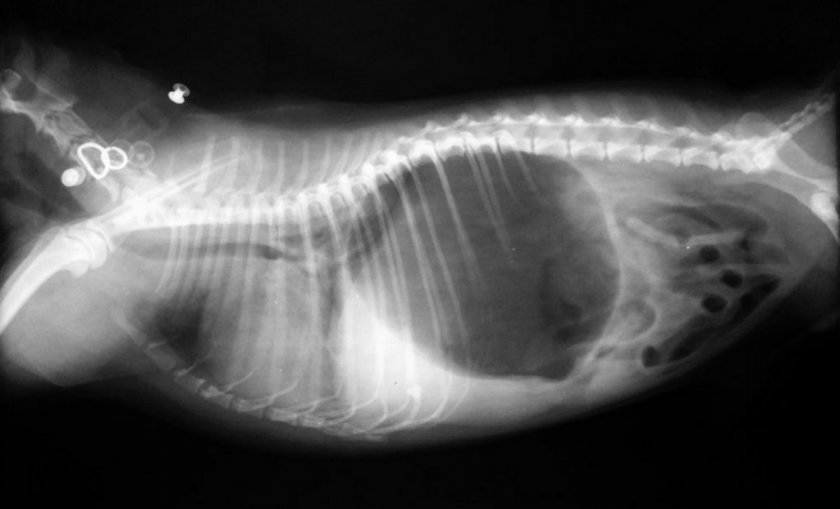

Заворот желудка

Заворот кишок (желудка) не зря считается очень страшной патологией, во многих случаях связанной со смертью собаки. Животные крупных пород (например, доги, ротвейлеры или мастифы) имеют врождённую предрасположенность к ней, а на спасение домашнего любимца у владельца часто всего несколько часов. Основные признаки патологии следующие:

- непродуктивная рвота, позывы к ней;

- увеличение объёмов живота из-за скопившихся в нём газов;

- повышение слюнотечения;

- одышка;

- потемнение каловых масс;

- сильное беспокойство животного.

Если своевременно не предпринять какие-либо меры для нормализации состояния питомца, оно будет только ухудшаться, вызывая коллапс, побледнение дёсен, учащение сердцебиения и мышечную слабость, когда собака с трудом встаёт в начале на задние, а затем и на передние конечности.